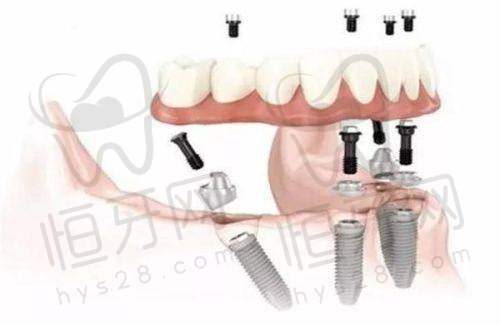

种植牙项目:种植牙是衢州开化可恩口腔门诊部的特色项目之一。随着人们生活水平的提高,对牙齿缺失修复的要求也越来越高。种植牙作为一种精良的牙齿修复方式,具有美观、舒适、耐用等优点。门诊部采用了精良的数字化种植技术,能够精细地确定种植位置和角度,提高种植的成功几率。医生们会根据患者的口腔情况和身体状况,为患者选择合适的种植体,确保种植成效自然美观,与真牙无异。

评价二:“我因为牙齿缺失,想做种植牙手术。在朋友的推荐下,我来到了衢州开化可恩口腔门诊部。医生在手术前给我做了详细的检查和评估,制定了个性化的种植方案。手术过程中,医生操作非常熟练,而且有精良的设备支持,整个手术特别顺利。术后,医生还定期回访我,关心我的修复情况,让我感觉特别贴心。现在我的种植牙已经修复得良好了,吃东西也特别方便。”